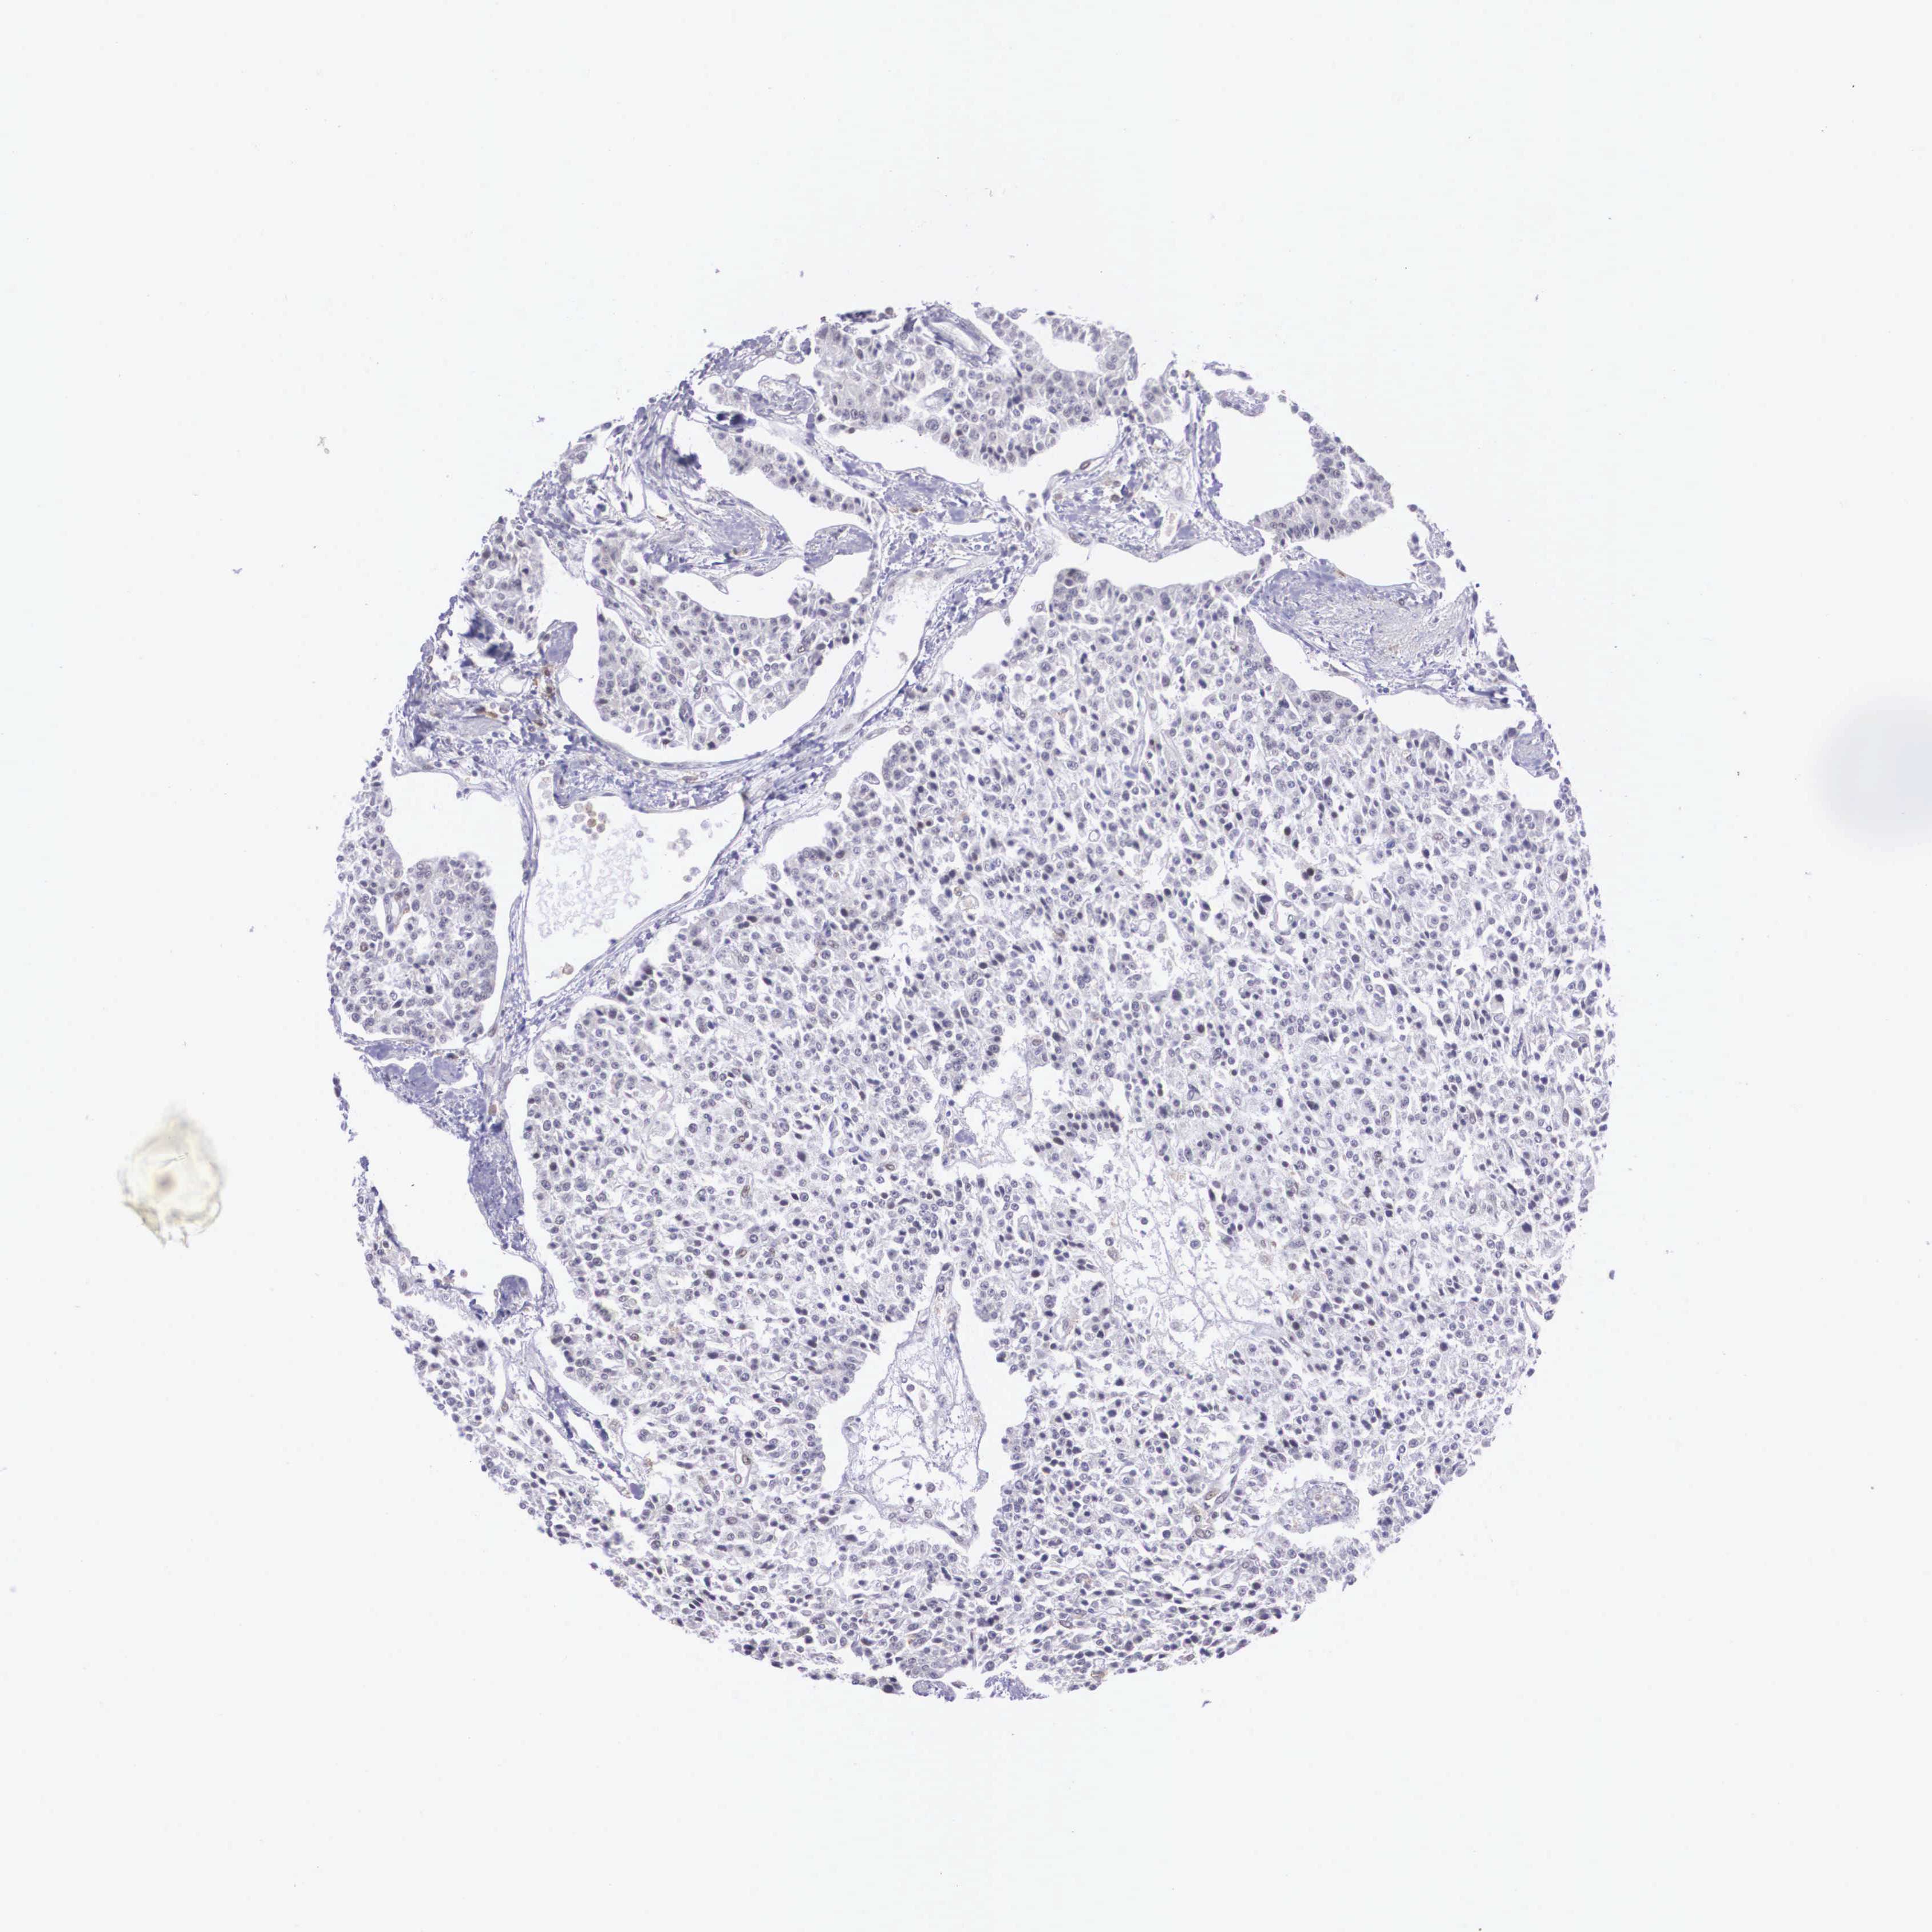

CARCINOID - Protein expressioni

A mouse-over function shows sample information and annotation data. Click on an image to view it in a full screen mode. Samples can be filtered based on level of antibody staining by selecting one or several of the following categories: high, medium, low and not detected. The assay and annotation is described here.

Note that samples used for immunohistochemistry by the Human Protein Atlas do not correspond to samples in the TCGA dataset.

Antibody stainingi

Antibody staining in the annotated cell types in the current human tissue is reported as not detected, low, medium, or high, based on conventional immunohistochemistry profiling in selected tissues. This score is based on the combination of the staining intensity and fraction of stained cells.

Each image is clickable and will lead to virtual microscopy that enables deeper exploration of all samples and also displays staining intensity scores, fraction scores and subcellular localization as well as patient and tissue information for each sample.

Antibody HPA000662

Staining

High

Medium

Low

Not detected

Intensity

Strong

Moderate

Weak

Negative

Quantity

>75%

75%-25%

<25%

None

Location

Nuclear

Cytoplasmic/membranous

Cytoplasmic/membranous,nuclear

Carcinoid, malignant, NOS